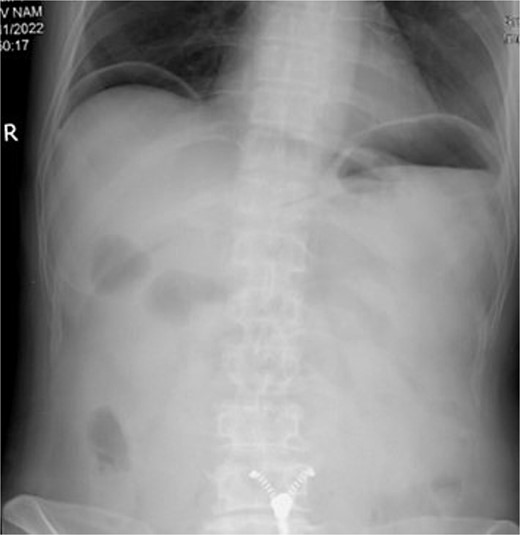

A 74-year-old man was admitted to the emergency department with severe, unremitting abdominal pain. Physical examination revealed guarding and rigidity. Plain abdominal X-rays revealed free gas under both hemi-diaphragms (Fig. 1). His medical history recorded arthritis, for which he has been treated with NSAID and corticosteroids for over 3 months. An indication of emergency laparotomy was performed for the patient with an initial diagnosis of generalized peritonitis due to gastrointestinal perforation.

X-ray showing free air under both hemi-diaphragms, indicative of gastrointestinal perforation.

Peptic ulcer perforation remains a prevalent surgical emergency with significant morbidity and mortality, particularly among elderly patients [6, 7]. Clinical symptoms and signs of peptic perforation can be various amongst patients, but this case illustrated typical symptoms with sudden onset of abdominal pain with guarding and rigidity. The X-ray image of free air under both hemi-diaphragm reenforced the diagnosis.